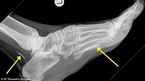

1m 길이의 기생충을 발에 4년이나 방치했던 한 아프리카 남성의 충격적인 사연이 알려졌다. 영국 일간지 데일리메일은 12일(이하 한국시간) 4년 전 호주로 이민 온 수단 남성의 발에서 1m 길이의 기생충 두 마리가 발견됐다고 전